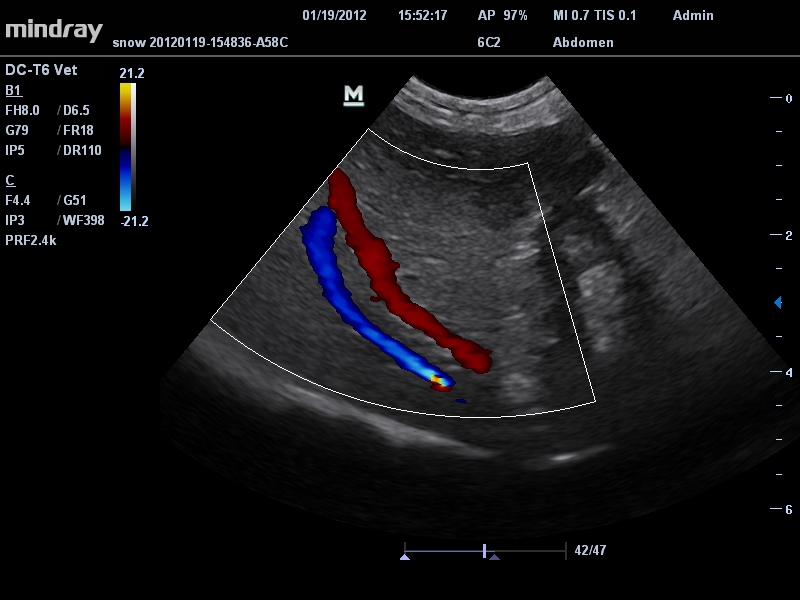

УЗИ-аппарат

Mindray DC-T6

Ультразвуковая система Mindray DC-T6 – это инновационный аппарат для проведения высокого уровня диагностики с качественной визуализацией и широким спектром применения. Платформа рекомендована для использования в коммерчески многопрофильных медицинских учреждениях и государственных лечебных клиниках.

• Микроконвексный датчик Mindray 6C2